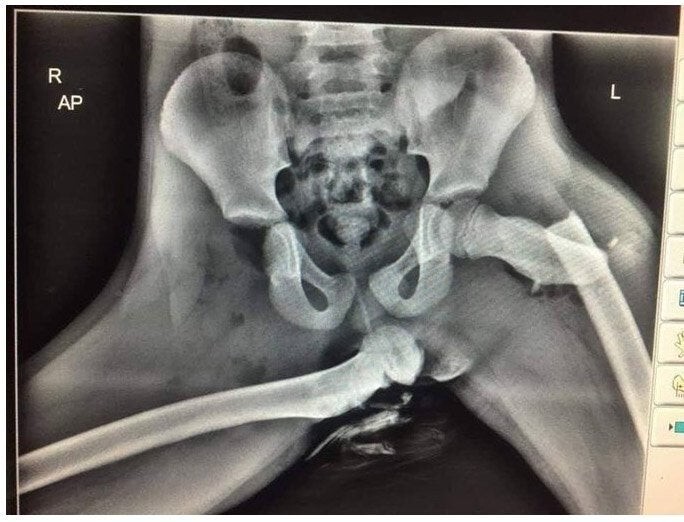

8. This X-ray of an accident participant shows why you shouldn't put your feet on the dashboard.